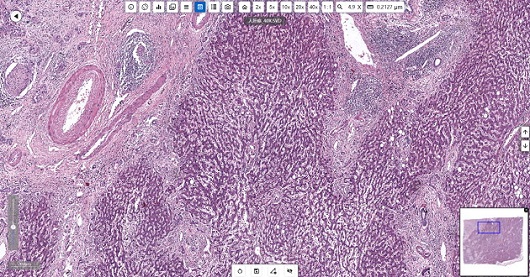

明美切片扫描仪MDS4扫描的人肝癌切片